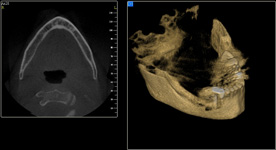

Jedná se o vyzvednutí membrány, která čelistní dutinu vystýlá, pod vyzvednutou membránou vznikne kapsa, kam se umístí augmentační materiál, do kterého se zavedou implantáty.

Vhojení implantátů se při této operaci prodlužuje na 6-12 měsíců.